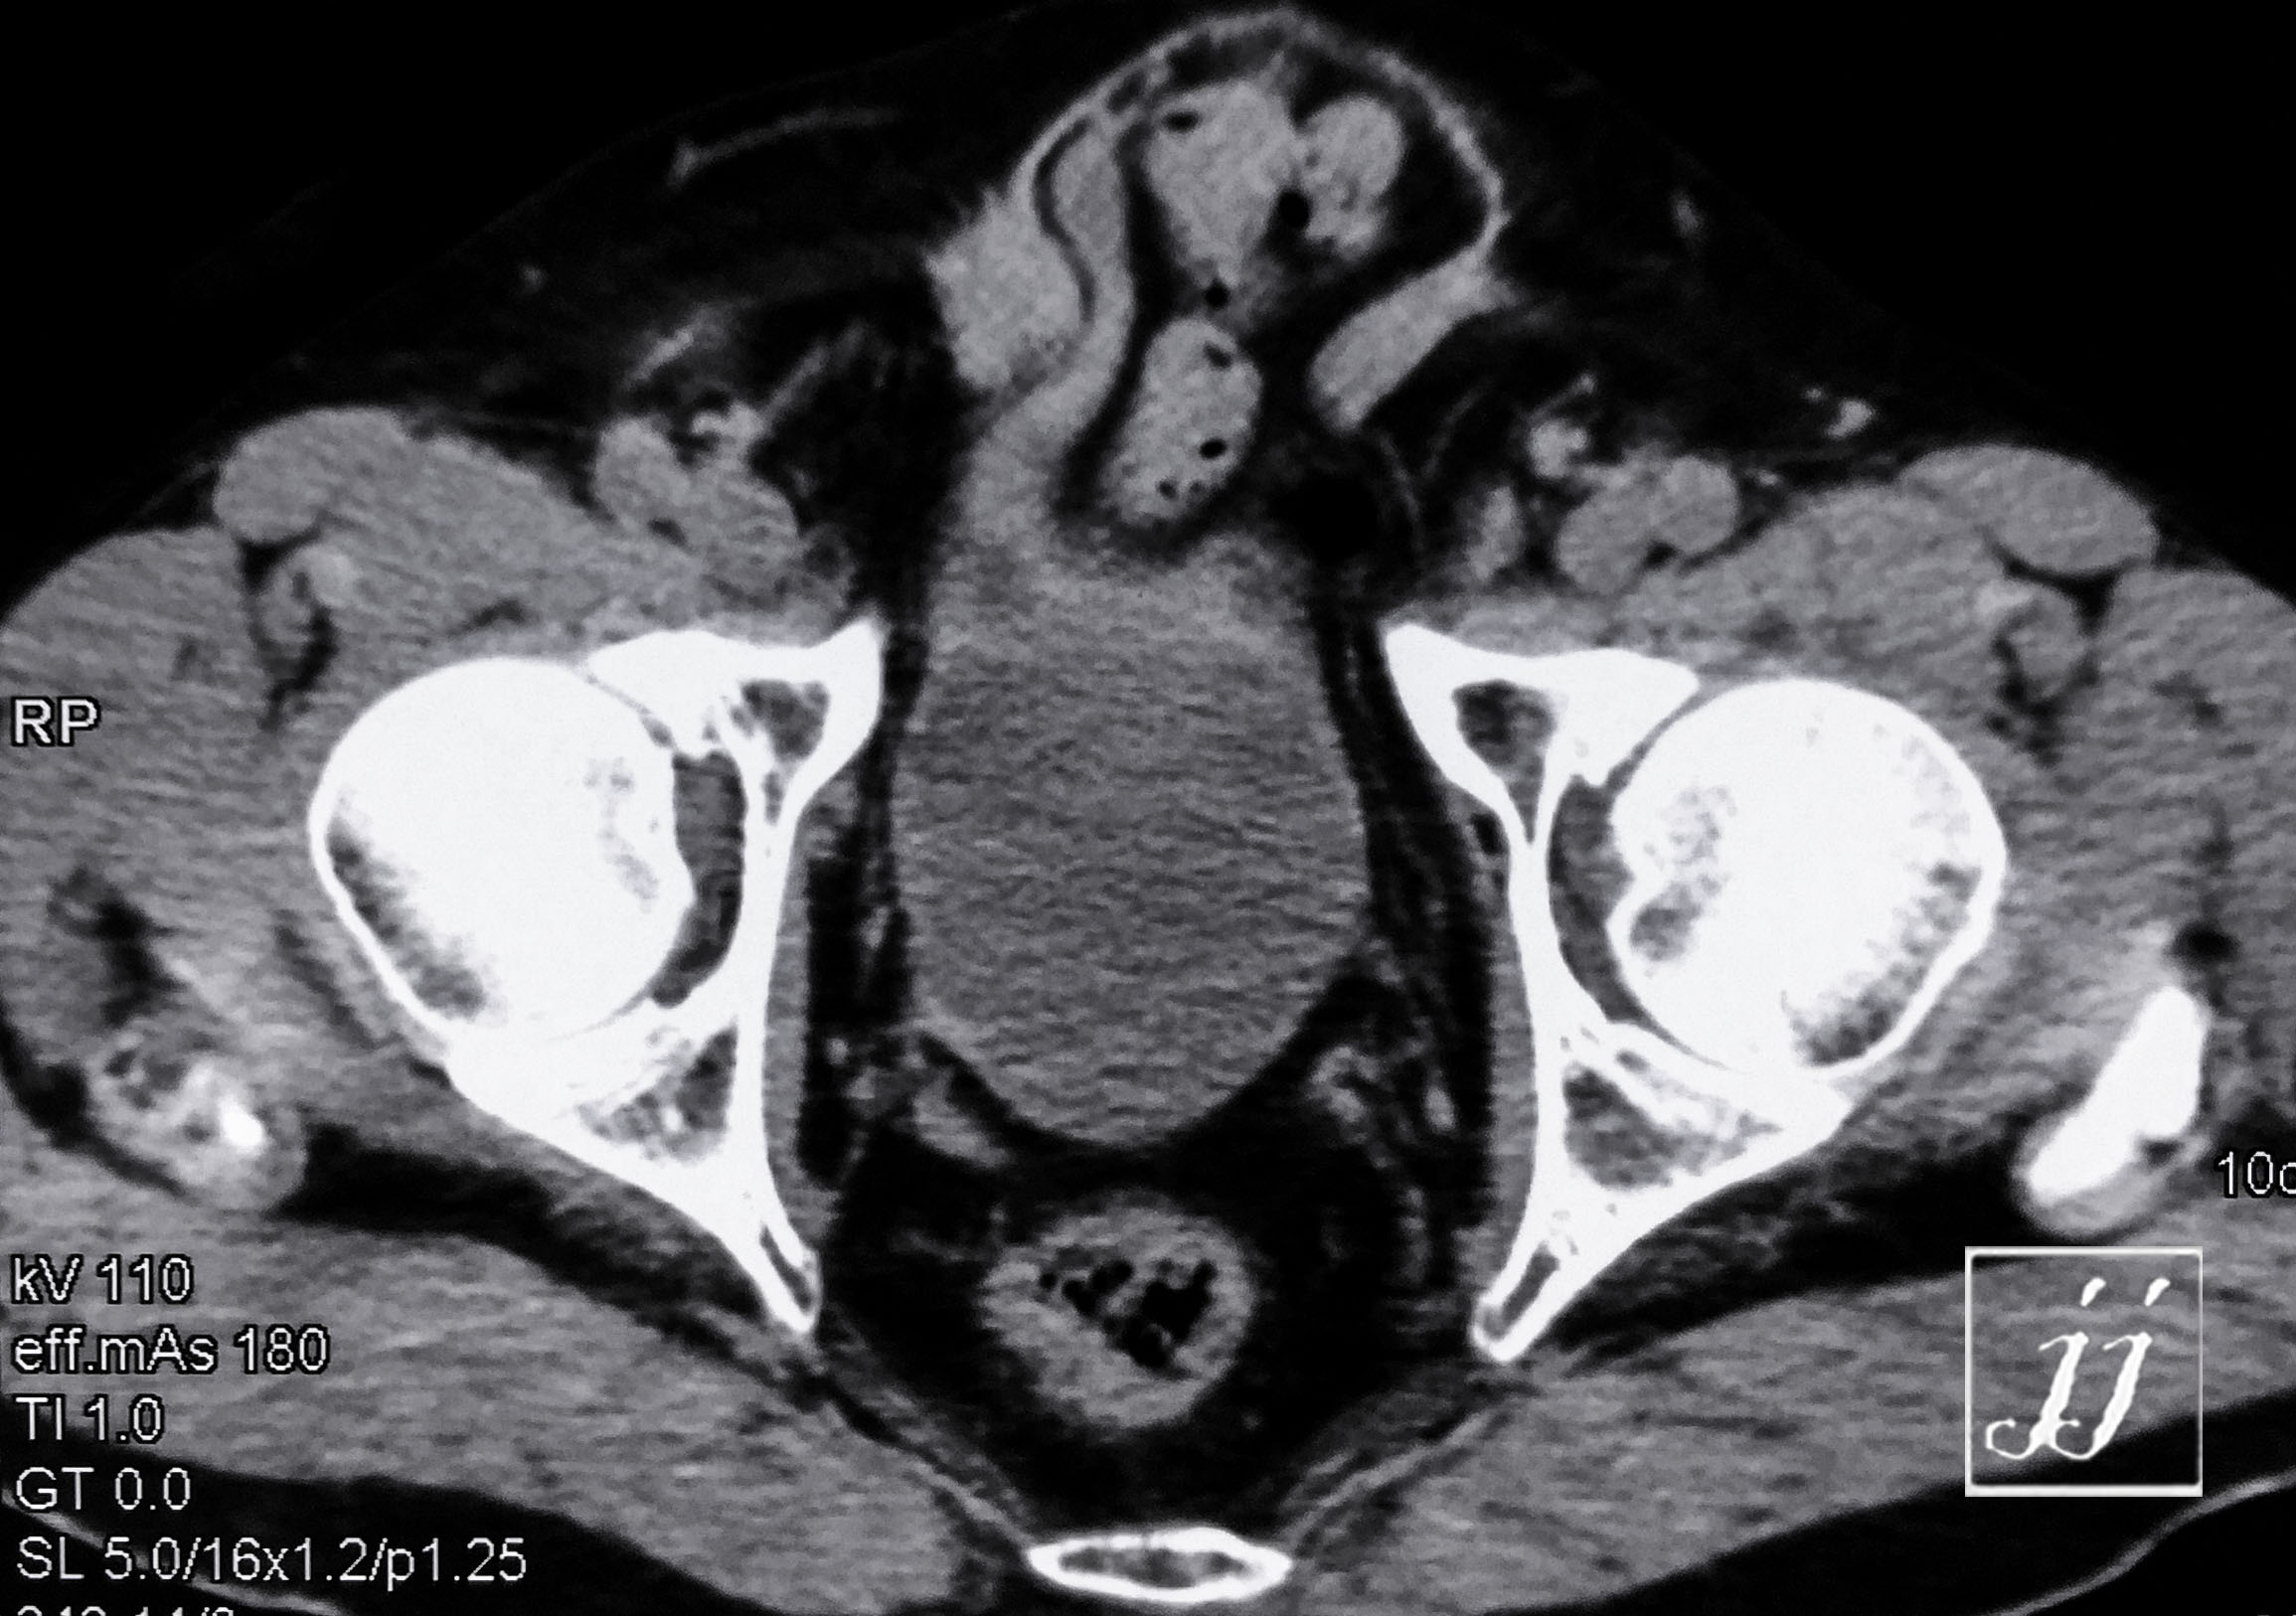

Abdomen- large left kidney cyst or tumor and inguinal hernia (3)